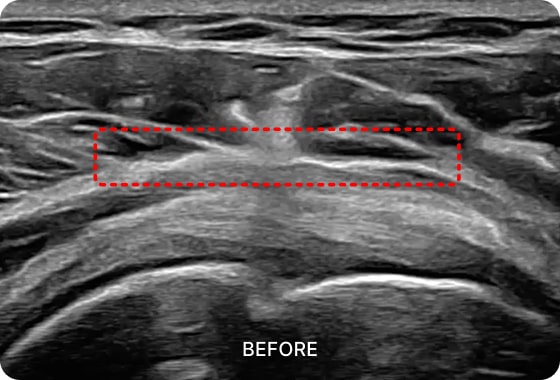

초음파 검사를 통해

회전근개 건염 통증의 직접적인

원인을 확인할 수 있습니다.

회전근개 힘줄의 염증과 두께, 파열, 석회화 정도를

정확하게 파악한 이후 치료 솔루션을 제시합니다.

01. PDRN 약침

PDRN 약침은 인체의 DNA와 90% 이상 유사한 구조로 세포 증식을 활성화하여

손상된 조직을 복구하는 효과가 뛰어납니다. 초음파를 활용하여 신경을 압박하는

염증을 박리하고 손상된 조직을 재생합니다.